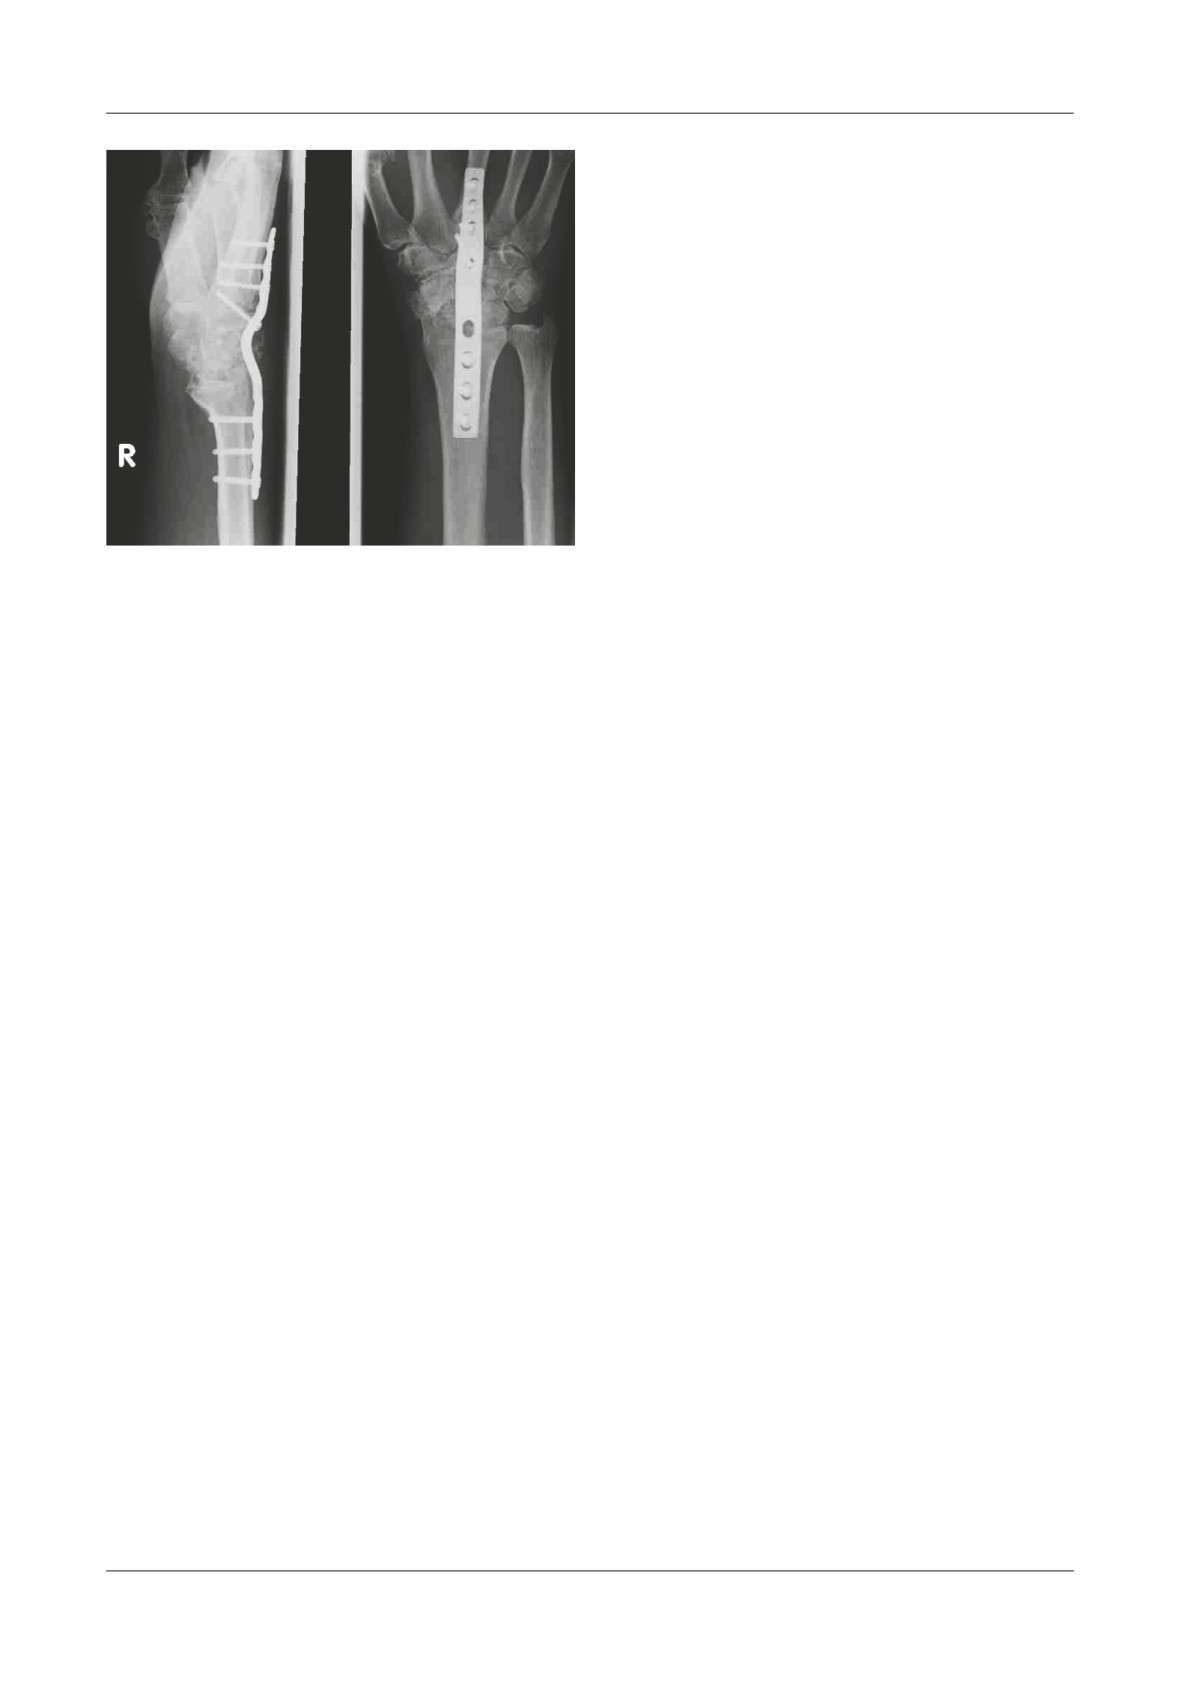

Figure 1. A. Anteroposterior pelvic X-ray of our patient where we can notice the sub trochanteric fracture and the lack of bone

density in that certain area. B. Intra operatory picture taken after the revision prosthesis has been placed.

C. Picture of the tumor mass that has been removed. Te only thing missing is the femoral head.